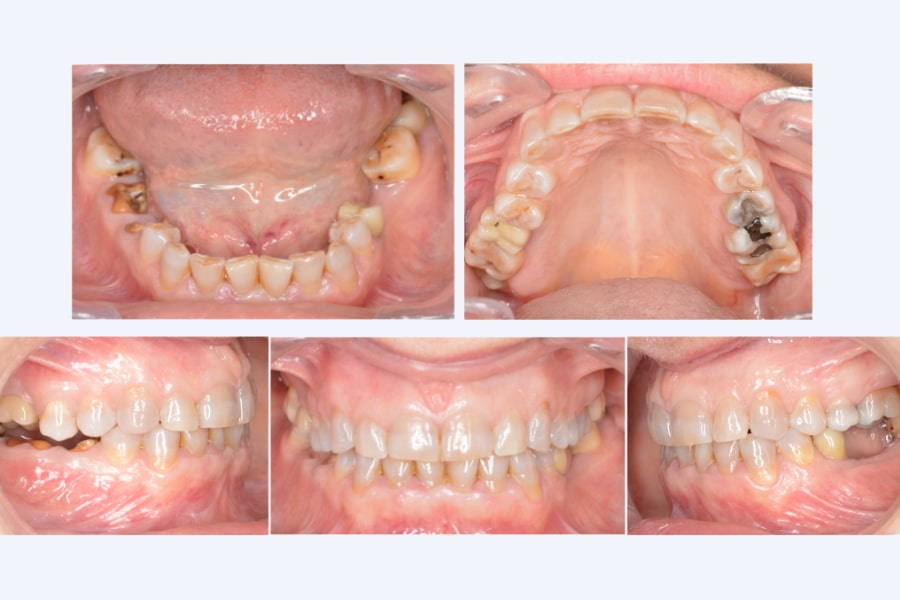

La paciente acudió a consulta por la pérdida de varias piezas posteriores, sensación de desgaste dental y molestias articulares al mover la mandíbula.

La ausencia de soporte en los dientes de atrás había alterado su mordida, provocando tensión muscular y un desgaste progresivo de los dientes anteriores. Esto afectaba tanto a la función masticatoria como a la armonía facial.

- Antes: pérdida de dientes posteriores, desgaste dental visible y molestias articulares frecuentes.

- Tratamiento: se inició una fase de estabilización mandibular con férula de desprogramación para aliviar la tensión muscular y recuperar el equilibrio articular.

Una vez alcanzada la estabilidad, se realizó una rehabilitación oral completa y mínimamente invasiva, combinando carillas de alta estética en el sector anterior con coronas de zirconio monolíticas sobre dientes e implantes. Este abordaje devolvió la función y la estética sin desgastar en exceso las piezas naturales.

- Después: la paciente recuperó una mordida estable, sin molestias articulares, y una sonrisa uniforme, funcional y natural.